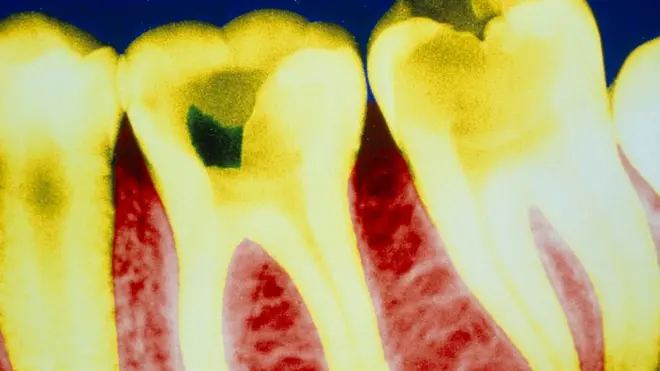

La caries es la enfermedad dental crónica más común en el mundo: afecta al 60-90% de los niños del mundo, según la Federación Mundial de Odontología.

Como enfermedad, es 20 veces más común que la diabetes y cinco veces más común que el asma.

Y, si no se trata adecuadamente, puede causar dolor y abscesos, requerir tratamiento de raíz y hasta la extracción de los dientes, lo que puede traumatizar a los niños de por vida.

La forma habitual de tratar la caries dental es perforar la podredumbre y luego cubrir el diente con una tapa delgada de acero inoxidable.